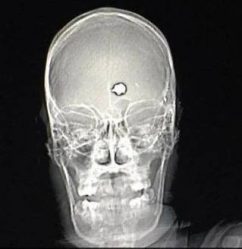

В Бодайбо 12-летний мальчик выстрелил в 7-летнего ребёнка из пневматической винтовки

В Бодайбо 18 августа семилетний ребёнок проводил время с приятелем возле улицы Нагорной.

Внезапно они услышали громкие хлопки и, заинтересовавшись, подошли ближе к источнику звука. После очередного хлопка мальчик ощутил резкую боль в области живота и поспешил домой. Спустя некоторое время он обратился за медицинской помощью вместе с матерью, где врачи выявили у него проникающее ранение, о чём сообщили представители пресс-службы ГУ МВД России по Иркутской области.

Выяснилось, что к инциденту имеет отношение 12-летний ученик школы. В тот день он вместе с двумя своими друзьями в возрасте от двенадцати до пятнадцати лет решил попрактиковаться в стрельбе на улице, используя две пневматические винтовки. По предварительным данным, их мишенью было заброшенное строение. В момент одного из выстрелов пуля случайно попала в семилетнего мальчика. Подростки заметили, как двое детей выбежали из здания и скрылись в неизвестном направлении.

В связи с данным происшествием прокуратура проводит расследование. Было инициировано уголовное дело по части 2 статьи 111 УК РФ, касающейся умышленного нанесения тяжкого вреда здоровью. Виновный подросток был взят на профилактический учёт. Материалы, собранные сотрудниками полиции в отношении всех несовершеннолетних участников инцидента, будут переданы на рассмотрение Комиссии по делам несовершеннолетних и защите их прав для принятия необходимых мер.